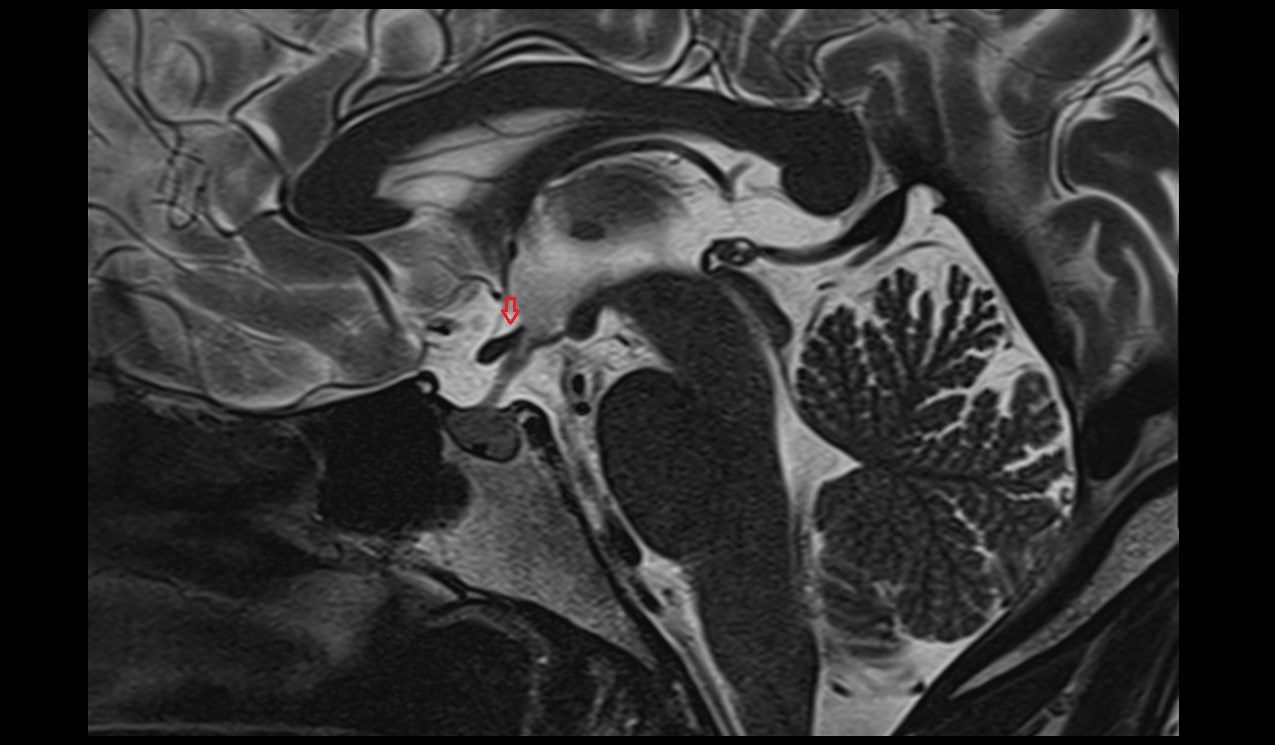

- Pituitary stalk